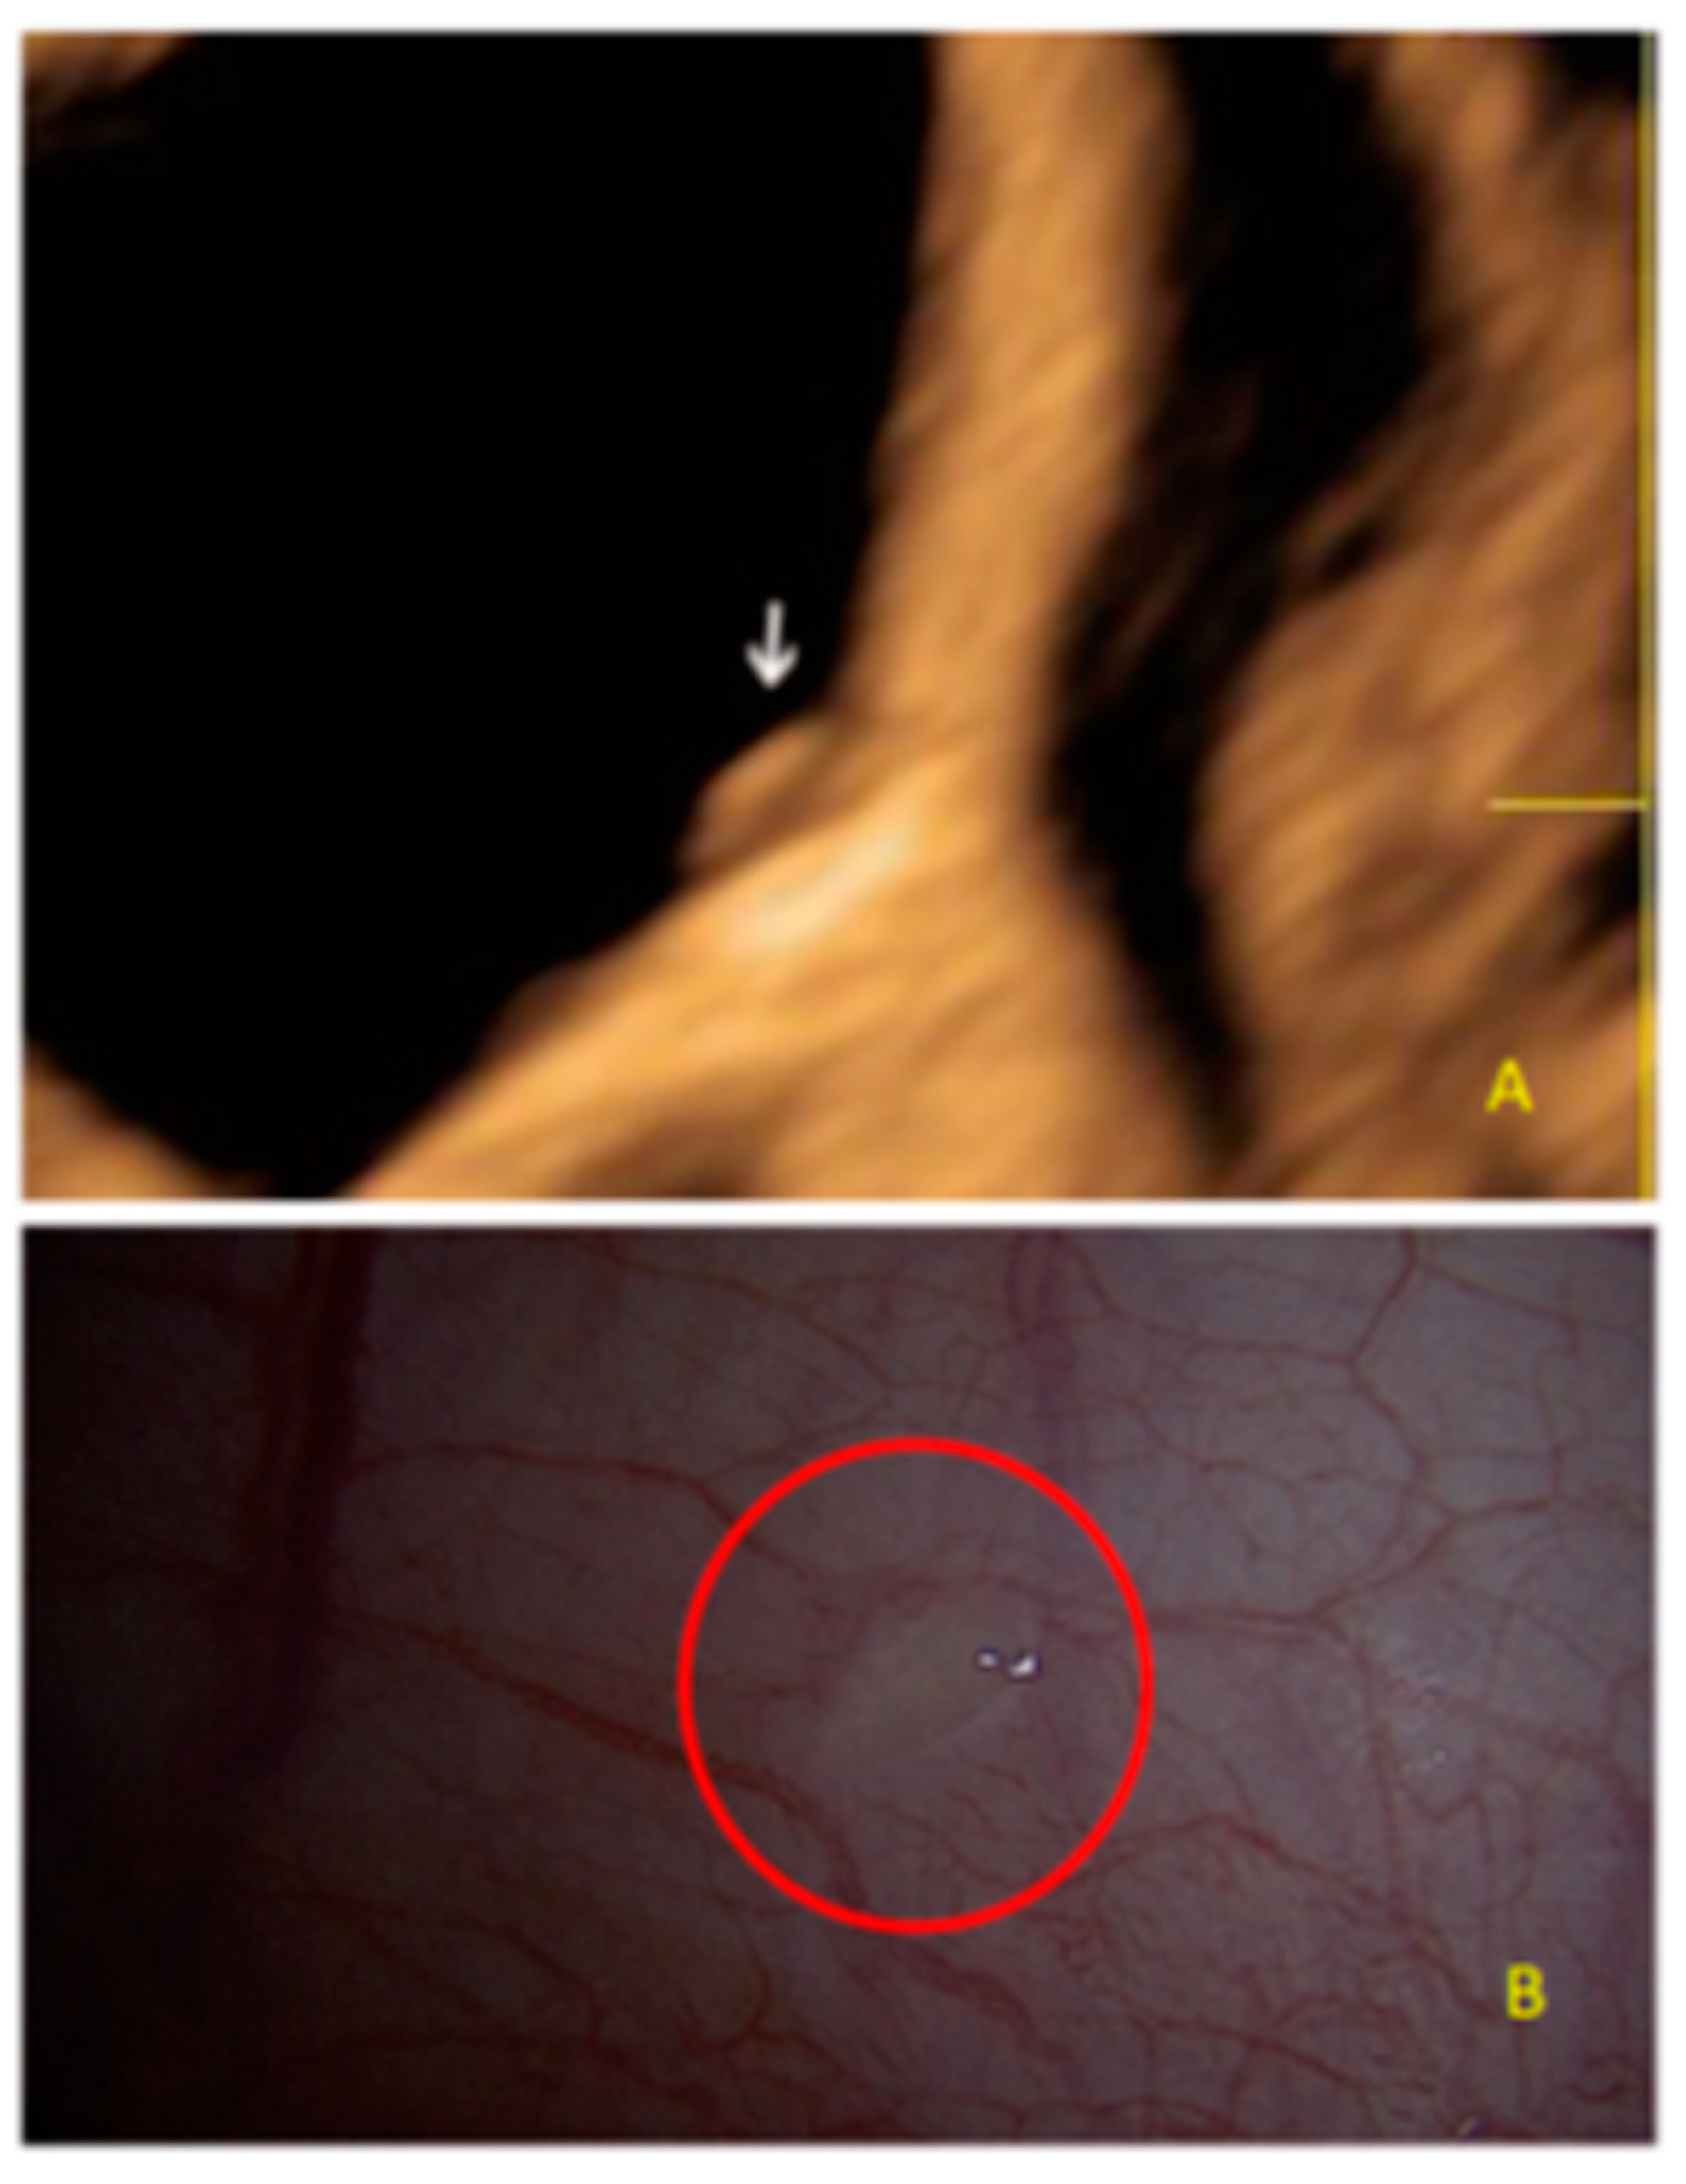

- The lesion may be convex, protruding from the peritoneal surface into the peritoneal cavity (we called this “bulging”), or it may appear as a concave defect in the peritoneum (we called this a “pocket”).

- The presence of hyperechoic foci (we called this a “pearl”).

- The presence of velamentous (filmy) adhesions associated to the lesion (we called this a “veil”).